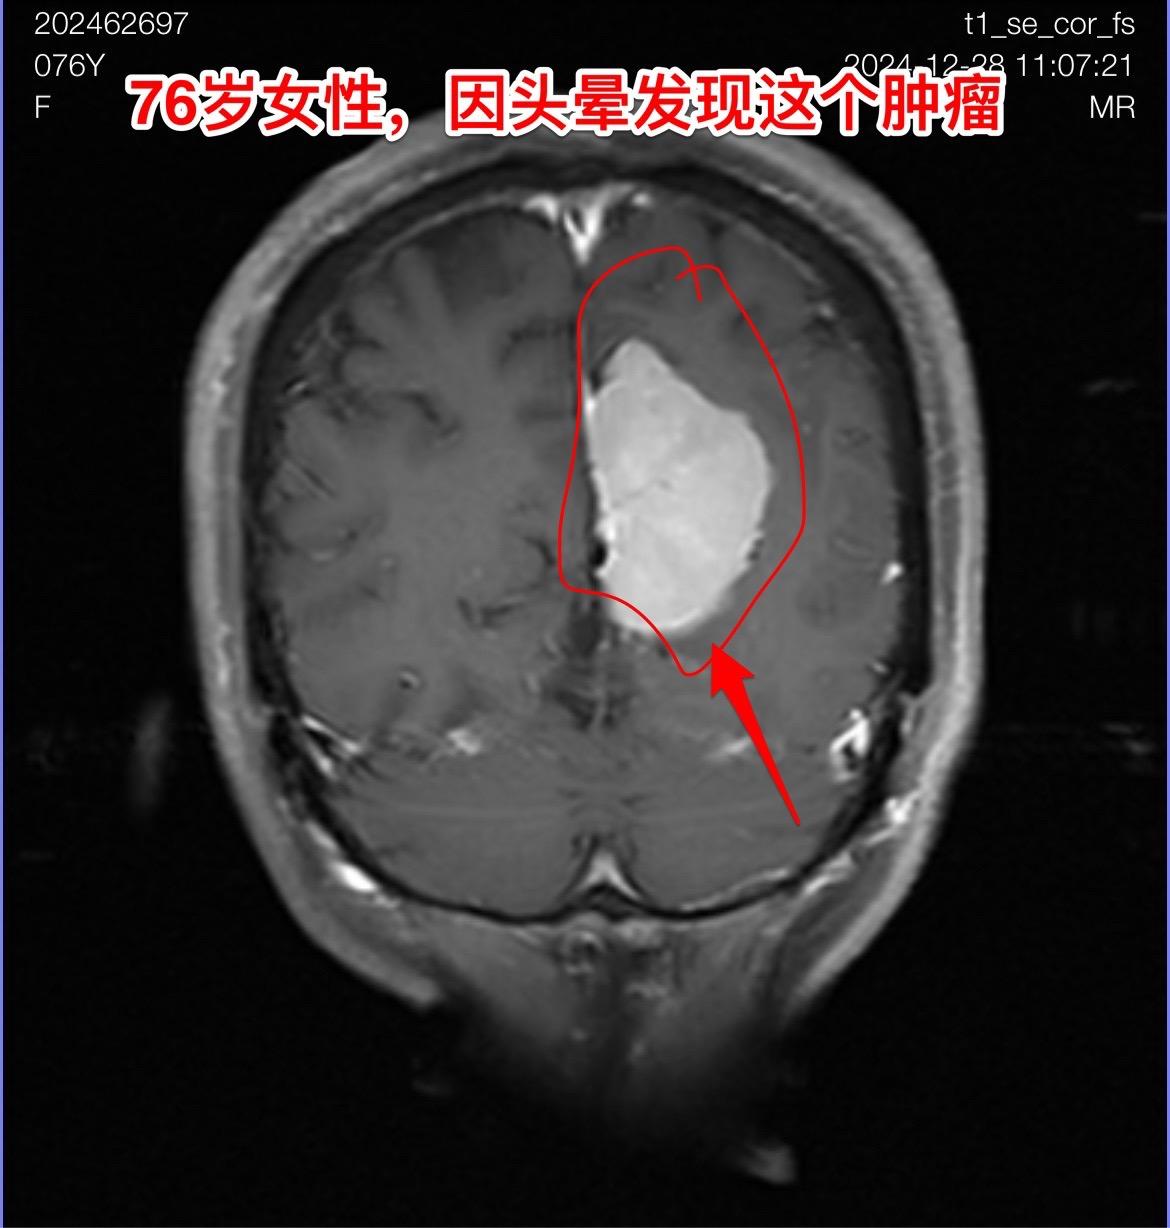

76岁女性,发现脑肿瘤需要作手术吗?山东省菏泽市的76岁女性,因头晕症状到医院去 头部磁共振检查,结果发现脑部长了一个大肿瘤,见图。 家人急切地想知道:是不是要立即动手术? 病人两年前还作过乳腺癌手术和甲状腺肿瘤切除手术。还有糖尿病病史20年。体重只有八十来斤。 这个老人需要立即作手术吗? 我看磁共振照片后印象是脑膜瘤。鉴于病人的身体状况不好,高龄,症状也不重,我建议先观察一段时间,不急于作手术。 朋友们,你们的意见是什么?